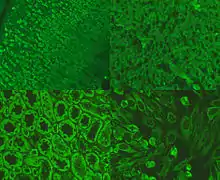

Anti-mitochondrial antibodies (AMA) are autoantibodies, consisting of immunoglobulins formed against mitochondria,[1] primarily the mitochondria in cells of the liver.

The presence of AMA in the blood or serum of a person may be indicative of the presence of, or the potential to develop, the autoimmune disease primary biliary cholangitis (PBC; previously known as primary biliary cirrhosis). PBC causes scarring of liver tissue, confined primarily to the bile duct drainage system. AMA is present in about 95% of cases.[2] PBC is seen primarily in middle-aged women, and in those afflicted with other autoimmune diseases.